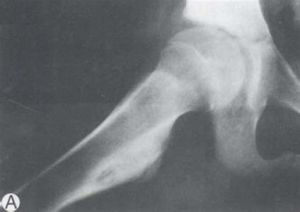

骨松質瘤則常發生於長骨端骨幹與骨骺交界處的軟骨部,隨管狀骨長度的增長,骨瘤亦有變化,呈不同形狀。

一般全身骨骼發育成熟後,即停止生長。但在發育過程中,如骨瘤引起骨骼受壓迫,仍可引致畸形生長。

骨疣常帶蒂,軟骨部可鈣化,呈菜花狀。